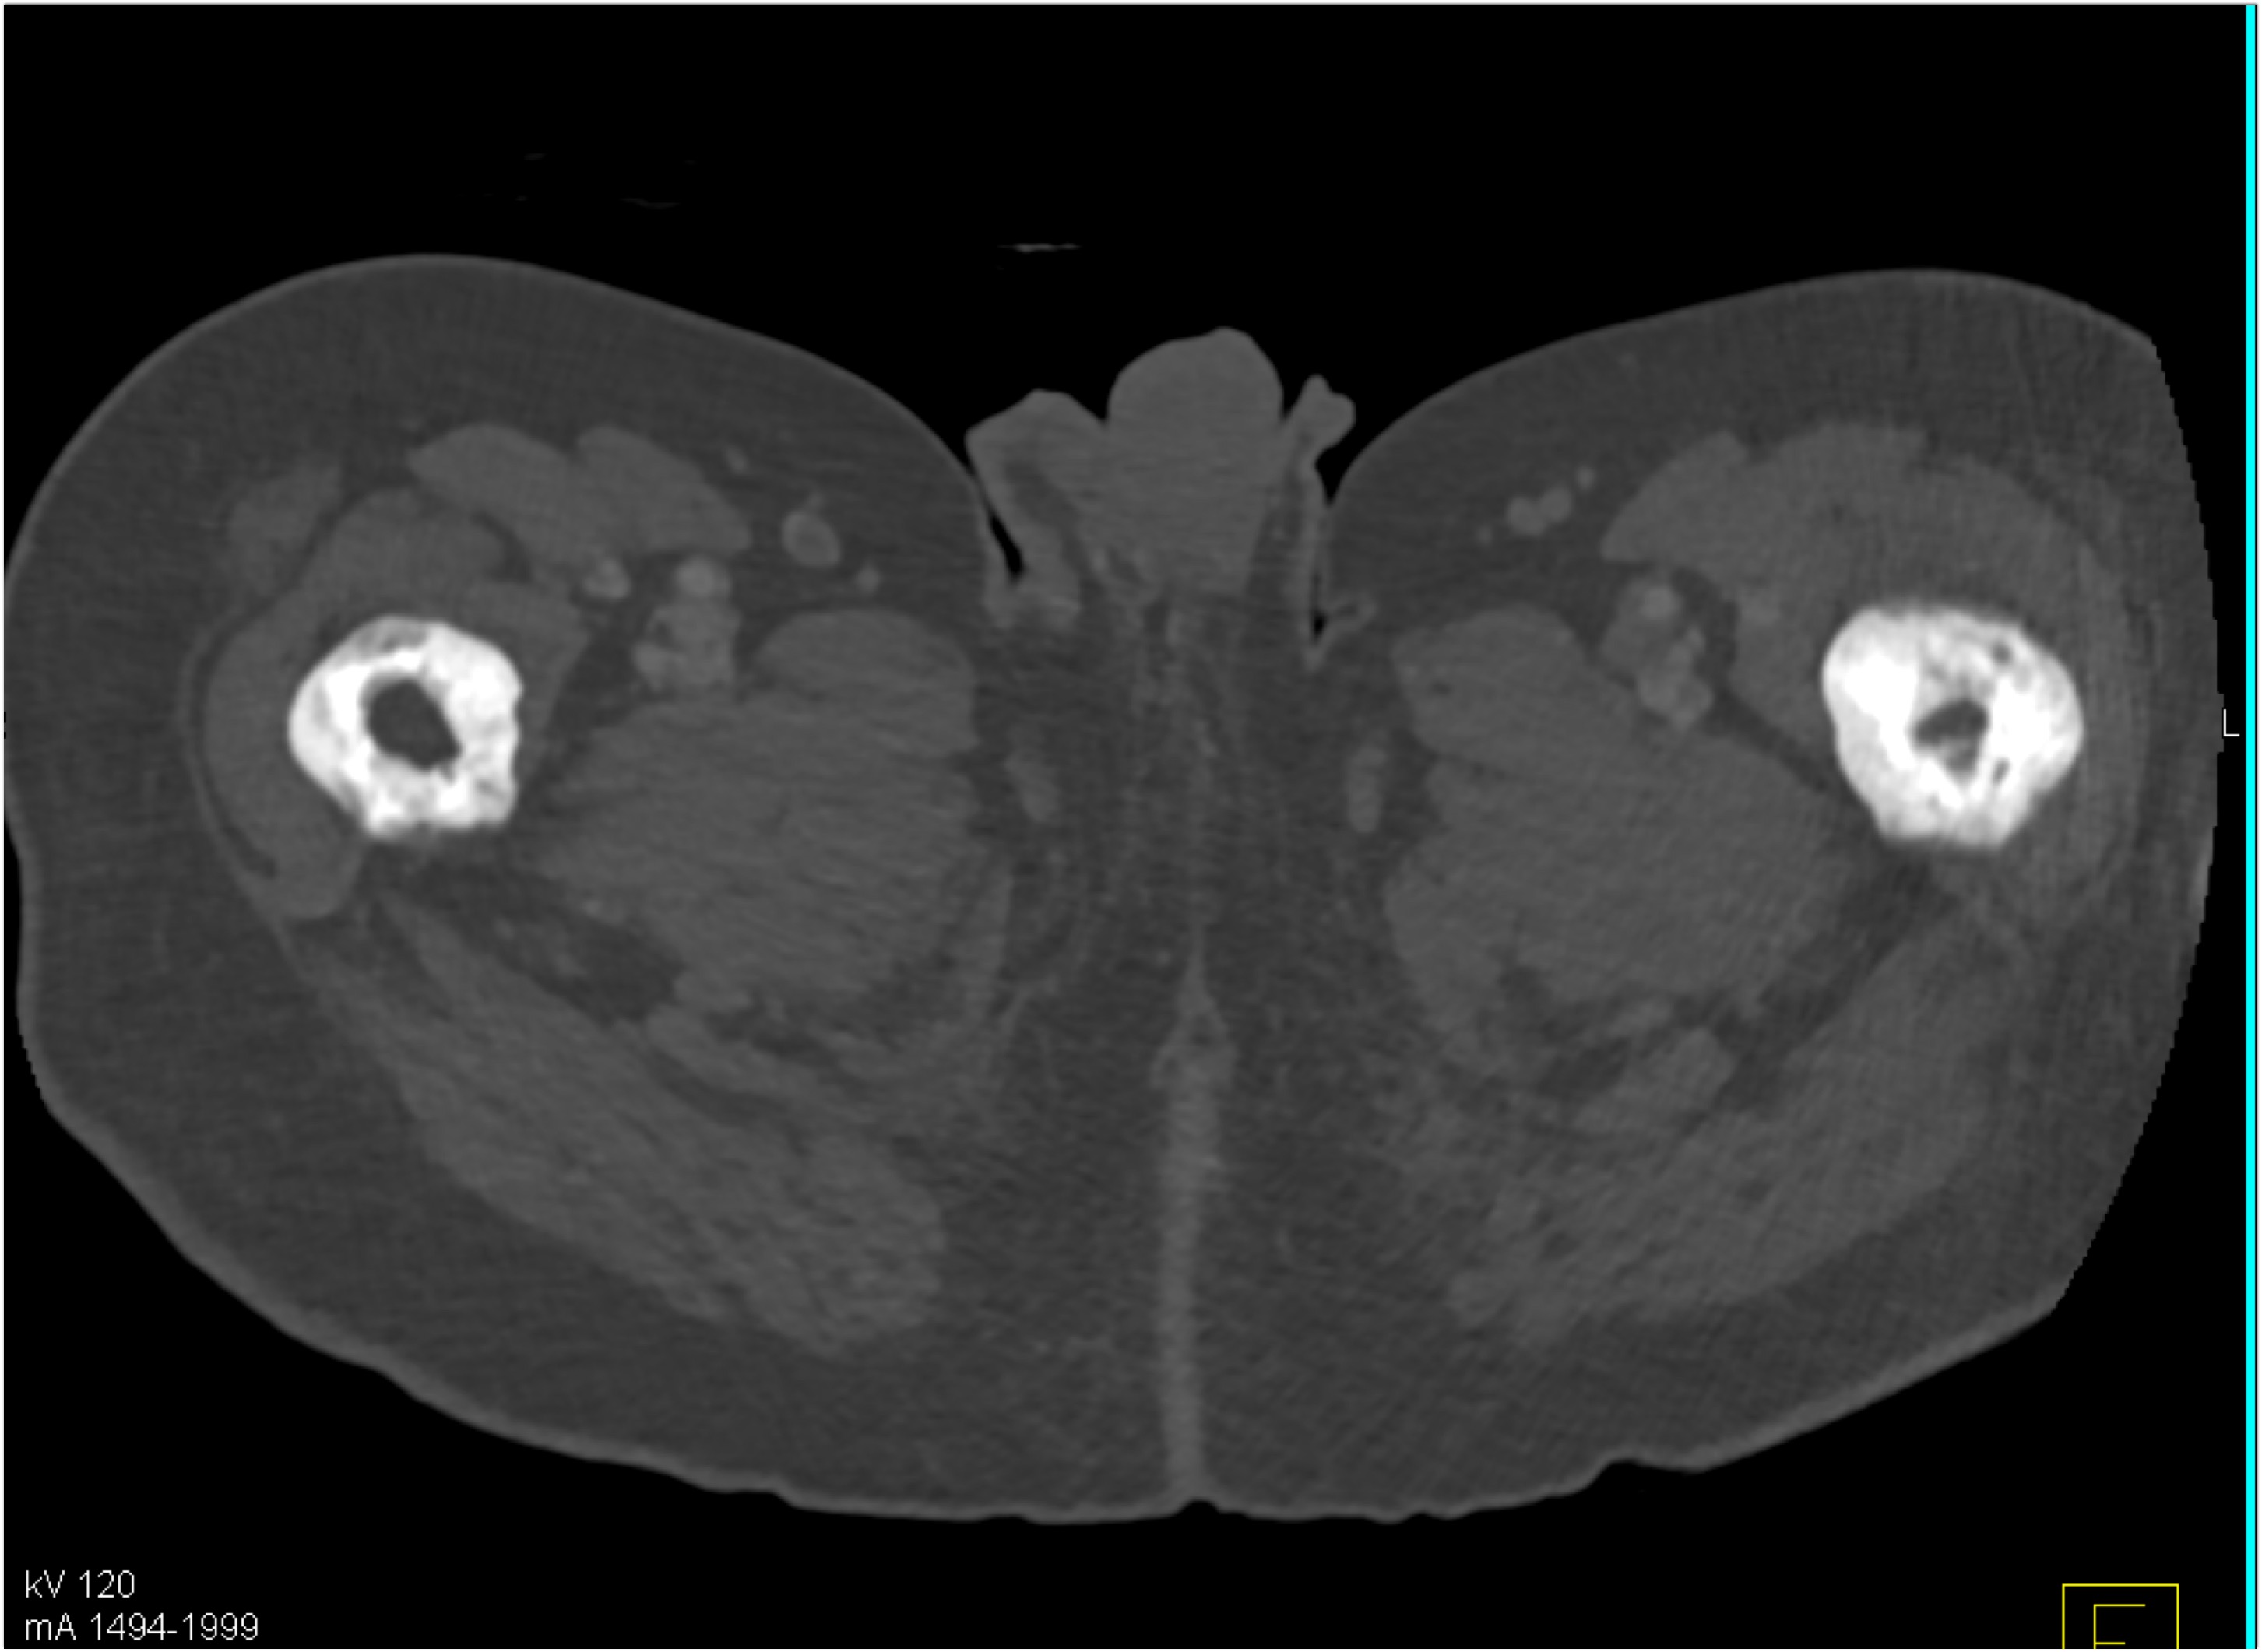

9) The best diagnosis in this 30ish year old female is?

renal cell carcinoma

MEST tumor (mixed epithelial and stromal tumor)

Wilms tumor

polycystic kidney disease